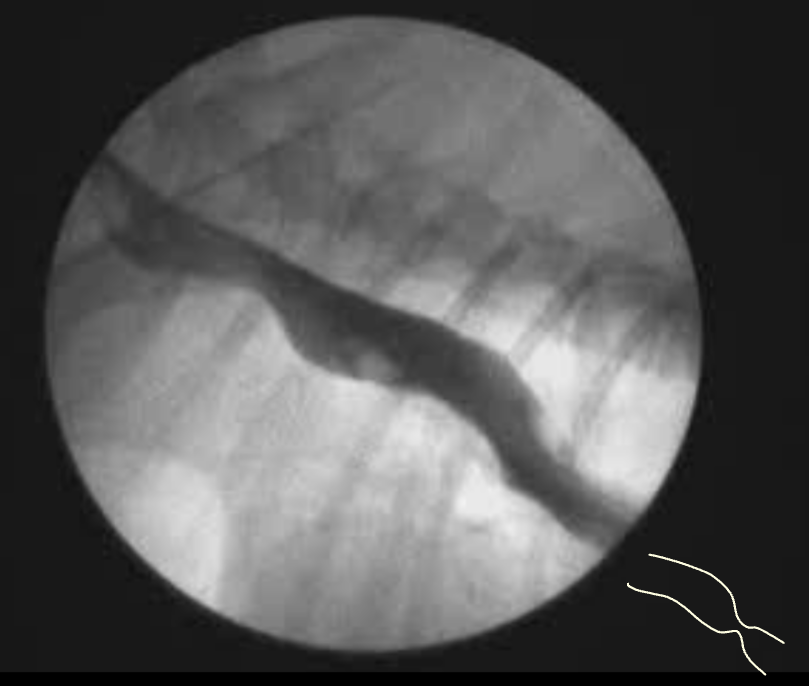

Foreign bodies (Esophageal FB)

- ์๋ ์ฃผ์์ ์ด๋ฌผ์ด ํ์ธ๋ ๊ฒฝ์ฐ ๋ด์ผ ํ๋ 2์ฐจ์ ๋ฌธ์

- ์๋ ์ฃผ์ ๊ฐ์ค์์ = ์๋์ฒ๊ณต โ ํ์(*fissure line), ํ๋ง์ผ and/or ํ๋ ด, ์ข ๊ฒฉ์ผ์ถ

- ์ค์ฐ์ฑ ํ๋ ด

- ์กฐ์ ๊ฒ์ฌ (๋น์ด์จ์ฑ ์กฐ์์ ์ฌ์ฉ)

- ๋ด์๊ฒฝ ์ฃผ์ โ ๊ธฐํ์ ์ํ ํํ์ฅ์ ์ต์ํ์ฌ ํ์ฌ ์ ๋ฐ

- ์๋ ์ด๋ฌผ์ ๋ฐฉ์ฌ์ ํ์ ํน์ง

- ์ด๋ฌผ ์ ํ๋ฐฉ์ gas๋ก ํ์ฅ๋ ์๋

- ํ์ผ์ ์ค๋ณต ์์ ๊ด์ฐฐ

- ์ฐ๋ถ์กฐ์ง์ฑ ์ด๋ฌผ์ ๊ฒฝ์ฐ, ์ฐ๋ถ์กฐ์ง ๋ฐ๋